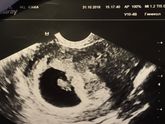

Вчера была на УЗИ

Увидела свою бусинку ?

Все хорошо ??

Правда в яичнике обнаружили кисту.

Врач сказал «ничего страшного, небольшая, сама рассосётся» ??